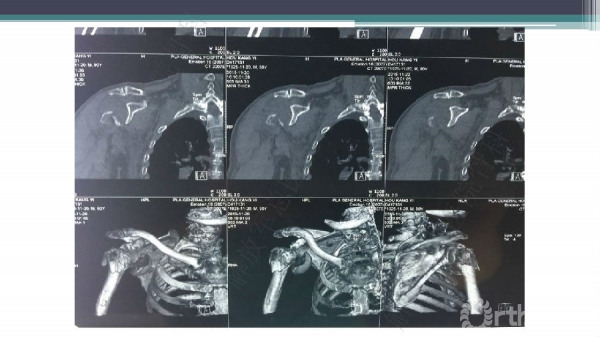

导 语:肱骨近端骨折仍是最常见的骨科损伤之一,尤其好发于老年人群。移位型肱骨近端骨折通常需要手术治疗,但是由于骨折粉碎、骨质较差,手术治疗往往会比较困难。随着锁定钢板的发明,使得并发症显著降低。但仍存在一些问题,对于内侧皮质不连续缺乏内侧可靠支撑,合并老年骨质疏松的病人,锁定钢板吊臂样结构就无法满足力学要求,随着康复锻炼可能出现断板、断钉、螺钉切出肱骨头等并发症。本期解放军总医院骨科专家们对老年肱骨近端骨折的问题与创新手术技术进行了详细讲解。